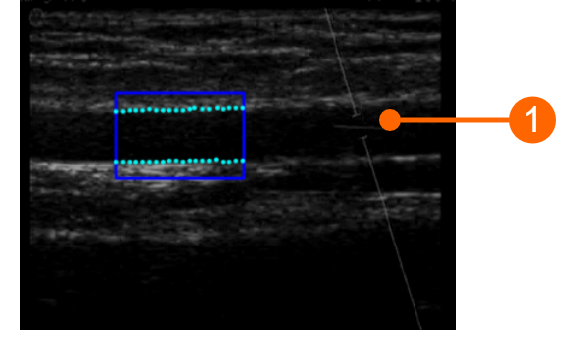

For FMD Studio we recommend an image depth of 2-3 cm. It is suggested also to choose a projection so that the vein is not visible (this normally appears immediately above the brachial artery). The algorithm for automatic tracking of the edges of the vessel could recognize the edge of the vein instead of the artery.

images/download/attachments/381258618/en_Ultrasound_Brachial-version-1-modificationdate-1759328517236-api-v2.png

Example of brachial artery image

The angle between the Doppler beam and the vessel orientation should be ≤60 degrees. The sample volume should be as wide as possible but without encompassing the vessel walls and allowing for a slight margin for error in case of movement. Pay attention that the cursor of the doppler sample volume is not into the ROI where the diameter is computed. It is recommended that the sample volume is 5 - 15 mm apart from the ROI.

images/download/attachments/381258618/cvs_setupDuplex_bmode_gliffy-version-1-modificationdate-1759328517224-api-v2.png

CAUTION: pay attention that nothing but the ultrasound image is into the ROI. Please note that the processing can be affected by annotations or any other graphical object that is superimposed to the image. In particular, pay attention that the cursor of the doppler sample volume is not into the ROI.